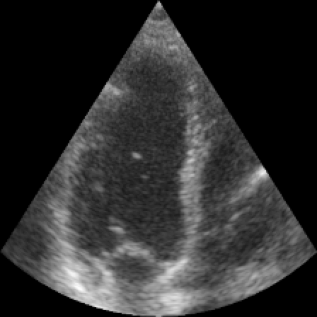

We propose a novel approach that adapts hierarchical vision foundation models for real-time ultrasound image segmentation. Existing ultrasound segmentation methods often struggle with adaptability to new tasks, relying on costly manual annotations, while real-time approaches generally fail to match state-of-the-art performance. To overcome these limitations, we introduce an adaptive framework that leverages the vision foundation model Hiera to extract multi-scale features, interleaved with DINOv2 representations to enhance visual expressiveness. These enriched features are then decoded to produce precise and robust segmentation. We conduct extensive evaluations on six public datasets and one in-house dataset, covering both cardiac and thyroid ultrasound segmentation. Experiments show that our approach outperforms state-of-the-art methods across multiple datasets and excels with limited supervision, surpassing nnUNet by over 20\% on average in the 1\% and 10\% data settings. Our method achieves $\sim$77 FPS inference speed with TensorRT on a single GPU, enabling real-time clinical applications.